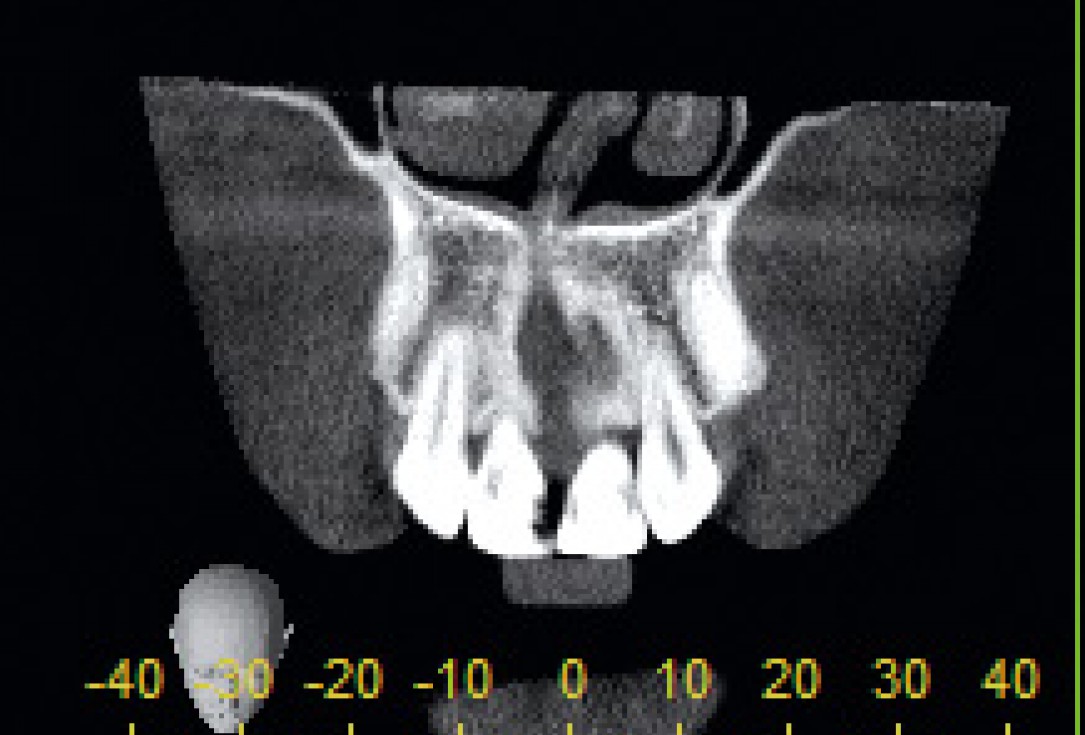

2/26 - CT scan reveals major bone loss in frontal maxillaBone augmentation in aesthetic zone with maxgraft® bonering - Dr. A. Patel

Initial situation: bone loss due to lack of physical load of bridge retained region 11